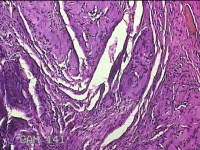

左示指肿物

性别

男

年龄

35岁

临床诊断

左示指末节肿物性质待查?

一般病史

发现左示指肿物

标本名称

大体所见

灰白暗红色肿物0.7x0.3x0.2cm一个,表面糜烂,切面灰白暗红色,质软。

良性病变。